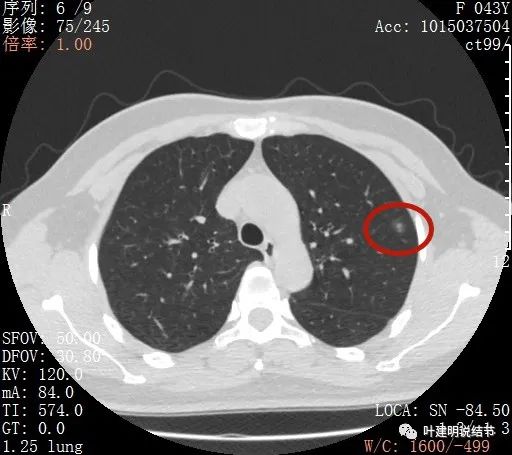

上图示病灶内部有高密度点状成分(粉色箭头所指)

同样示内部点状高密度,瘤肺边界清,密度显乱

上图显示混合磨玻璃结节,中间点状高密度区域,边上有微小血管征

上图示病灶边缘磨玻璃成分有的区域密度过低(绿色箭头),事后回头来看,磨玻璃部分的密度过低,不容易是浸润性腺癌,而更符合原位腺癌

上图示瘤肺边界处显模糊(砖色箭头),病灶内部仍是有偏高密度的点状成分

上图层面也显示病灶边缘欠清,有些模糊,虽总体轮廓还是比较清晰

从以上靶扫描图像上看,给人的印象是肿瘤范畴的结节,是混合磨玻璃结节,但磨玻璃部分的密度偏低,有的边缘显模糊,中间有点状高密度,也有微小血管进入,应该至少微浸润性腺癌可能性大。持续存在已经2月余,位置又还靠边上的,可考虑手术切除。下面再来瞧瞧后处理重建的图像: